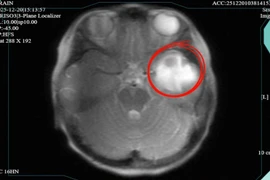

Theo Bệnh viện Nhi Thanh Hóa, rò xoang lê là bệnh lý bẩm sinh do còn tồn tại túi mang III, IV từ thời kỳ bào thai. Ở Việt Nam rò xoang lê chiếm tỷ lệ rất cao 51.92 – 73.68% trong các bệnh lý nang và rò mang bẩm sinh vùng cổ bên.

Bệnh này thường khởi phát chủ yếu ở trẻ em với biểu hiện u nang vùng cổ bên, áp xe vùng cổ tái diễn nhiều lần, sưng tấy, áp xe vùng tuyến giáp nên dễ nhầm với áp xe tuyến giáp, viêm tuyến giáp cấp mủ, áp xe hạch.

ro-xoang-le.png

Rò xoang lê ở trẻ - Ảnh BVCC